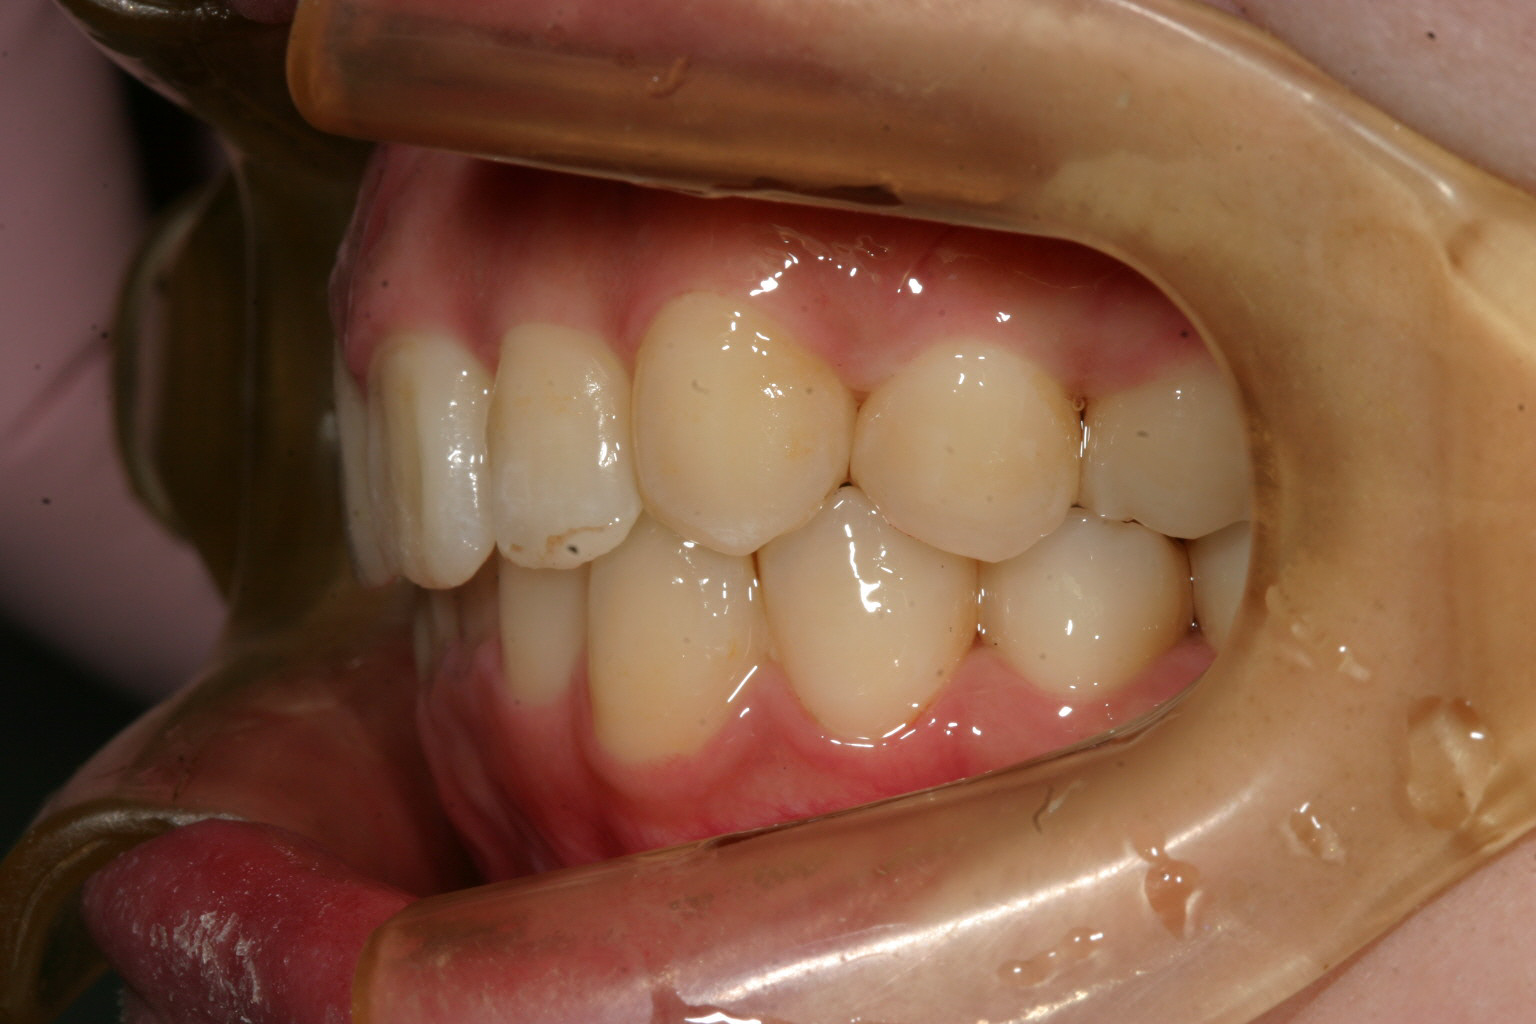

抜歯もせず綺麗なU字形に治りました。

でっぱも改善出来ました。

気になる出っ歯観も改善しました。